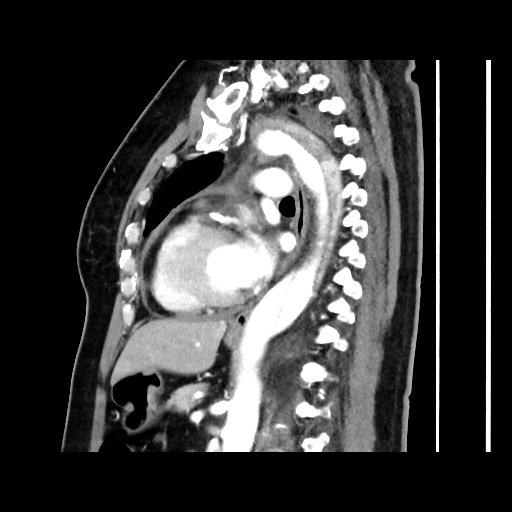

However, CK was found serially normal !!Symptom recurred on and off and BP fluctuate CT Aortogram was arranged and confirmed Type A Intramural haematoma and Type B aortic dissection. Patient transferred to CTSU, but conservative treatment adopted in view of recent PCI.Patient recovered well and discharge uneventfully Recent follow up was well and await follow up CT coro and aortogram.